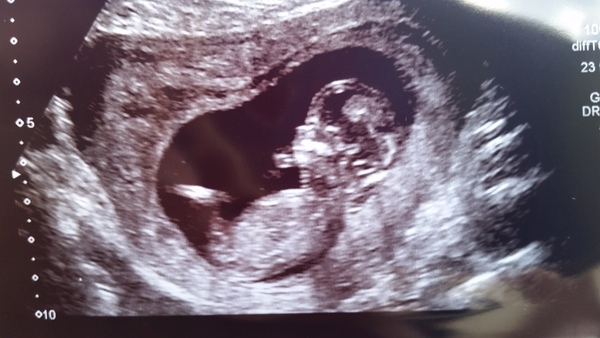

Here's my scan pic. Is actually much clearer but my camera is rubbish.

Tea any guesses on gender?

That is a cute pic! I think a little boy!

Is baby sucking their thumb in the pic?

Lovely pic overreaction I think a boy too!

Yeah that's a thumb sucking pic :-)

Two of my friends have said boy too.